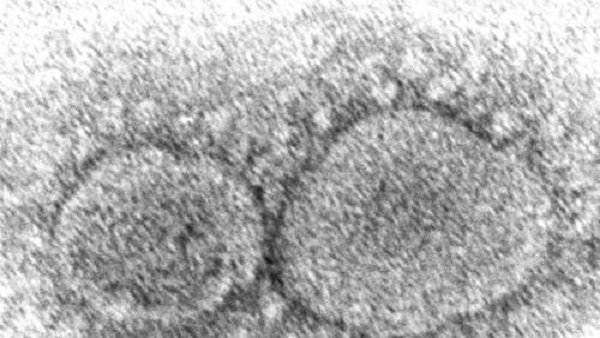

이스라엘 최대 코로나19 검사기관인 마이헤리티지랩은 "백신이 주요 감염경로인 코와 목구멍 주위의 바이럴 로드를 줄였다"며 "다만 초기 단계의 연구인 만큼 추가적인 조사와 연구가 필요하다"고 덧붙였습니다.